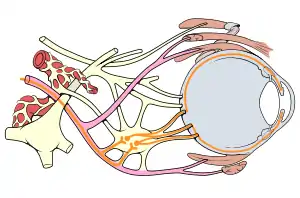

Mechanism

As the pair of oculomotor nerves arises from different subnuclei in the midbrain, courses through different structures in the brain and branches into superior and inferior divisions after exiting the cavernous sinuses, any lesions along its path will produce different pathological features of the third nerve palsy. The parasympathetic aspect of the nerve (which constricts pupils and thicken the lens) is located on the nerve surface, supplied by pial blood vessels. The nerve's core contains the main trunk of the oculomotor nerve, supplied by vasa vasorum. Thus pathologies affecting the nerve's core without affecting the superficial part of the nerve (thus sparing the pupillary reflex) are known as "medical" oculomotor nerve palsy. The "surgical" type of oculomotor nerve palsy is caused by external structures compressing on the nerve or trauma, which affects the entire nerve, thus affecting pupillary reflex.[2]

Ischemic stroke selectively affects somatic fibers over parasympathetic fibers, while traumatic stroke affects both types more equally. Ischemic stroke affects the vasoneurium, which starts to supply the nerve from outside to inside. As the somatic fibers are located in the inner part of the nerve, these fibres are affected more in the setting of ischemia. A similar mechanism is also accurate for diabetes. Therefore, while almost all forms cause ptosis and impaired movement of the eye, pupillary abnormalities are more commonly associated with trauma and the "surgical third" rather than with ischemia (the "medical third"). A posterior communicating artery aneurysm will generally cause compression of the entire third nerve and will this prevent any nerve signal conduction, affecting the somatic system as well as the autonomic. The compression of the external autonomic fibres renders the pupil nonreactive and leads to the "surgical third" nerve palsy.

Oculomotor palsy can be of acute onset over hours with symptoms of headache when associated with diabetes mellitus. Diabetic neuropathy of the oculomotor nerve in a majority of cases does not affect the pupil.[3] The sparing of the pupil is thought to be associated with the microfasciculation of the fibers that control the pupillomotor function located on the outmost aspect of the occulomotor nerve fibres; these fibres are spared because they are outermost and therefore less prone to ischemic damage than are the innermost fibres.[4]